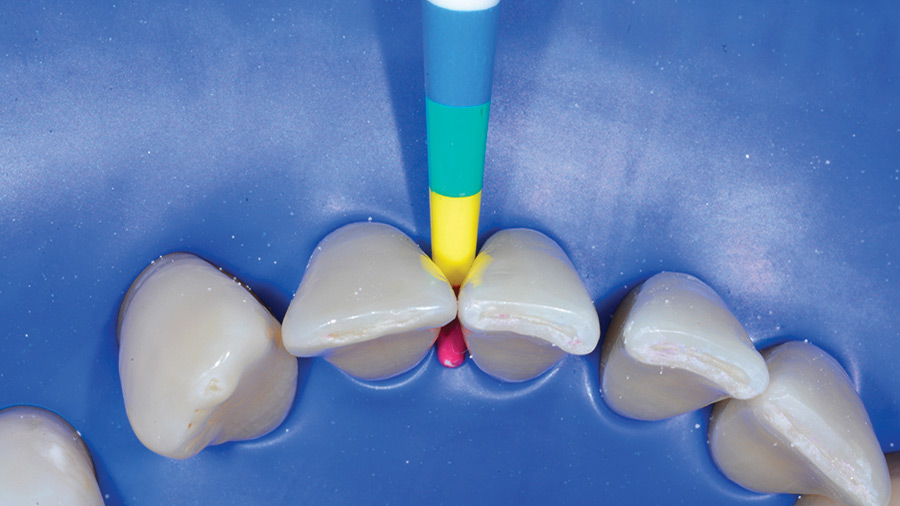

Introduction Orthodontic and periodontal therapy are intimately connected. To ensure a functional and aesthetically pleasing outcome the process begins with clinical assessment of many factors including periodontal probing depths, thickness of the attached gingiva, mobility, occlusion, furcation involvement and bleeding. This will ensure there are no underlying issues that could become aggravated by tooth movements.1,2 … Read more